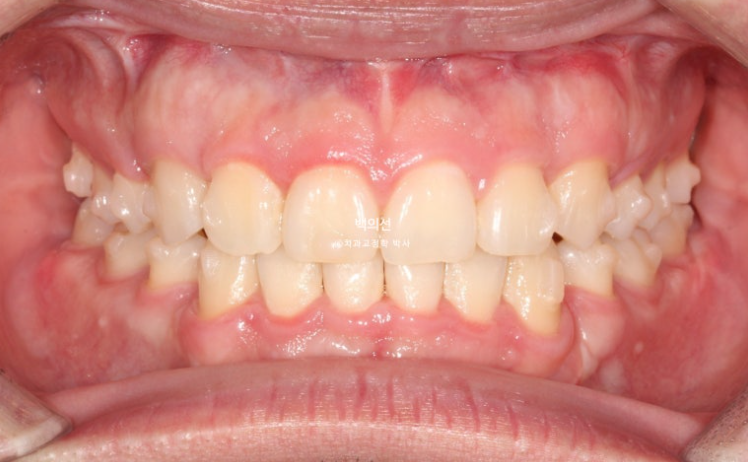

전 후 비교 보겠습니다.

24.10~25.08

남아있던 공간은 추가장치로 깔끔히 없어졌습니다.

25.08

치근흡수는 없으며 치근평행도는 좋습니다.

이제 전 후 비교 보겠습니다.

총 치료기간은 10개월, 재제작 1회 입니다.

앞니가 깊게 물리는 과개교합도 좋아졌습니다.